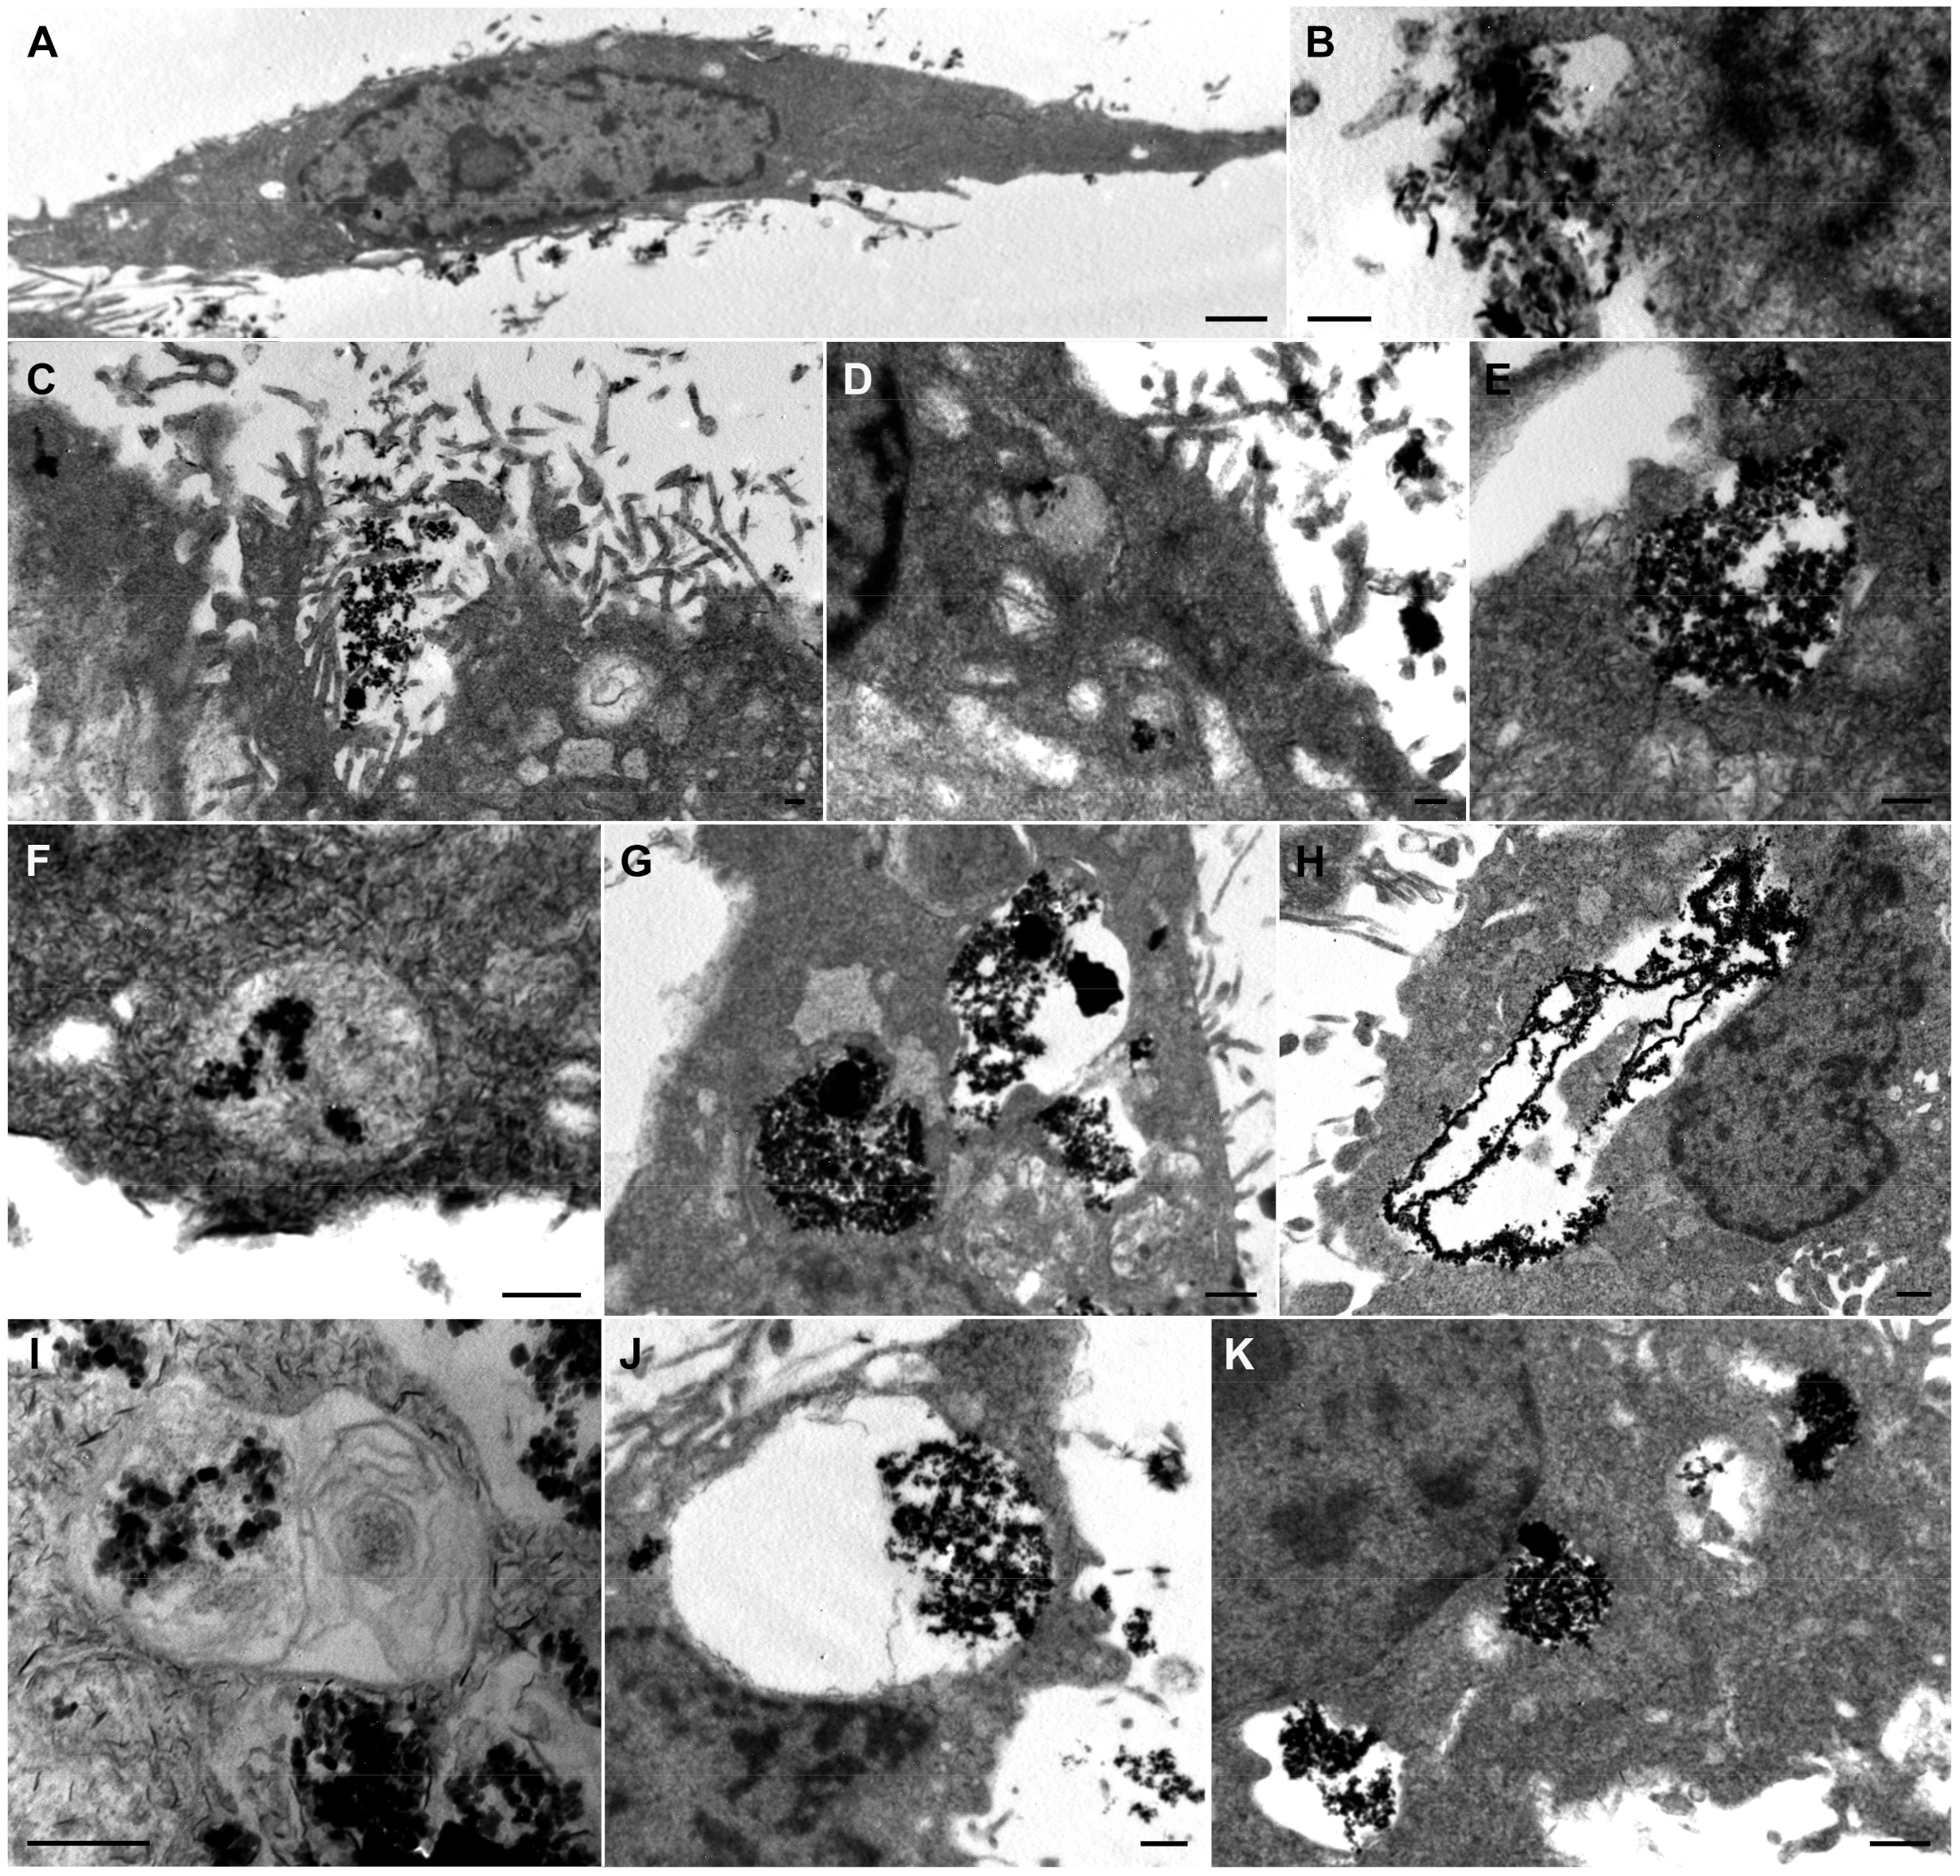

3.4. Analysis of the Cellular MNPs Uptake and Localization